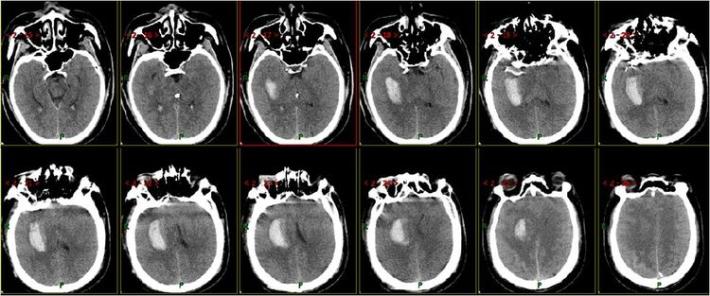

神经系统查体:神志清,精神差,饮水呛咳,双侧肢体肌力3级。NIHSS评分:11分。 于05.18 07:30(发病1小时)左右给予阿替普酶静脉溶栓治疗(具体不详),患者双侧肌力好转至4级,NIHSS评分改善至7分。 5月19日患者症状加重,出现意识水平下降, 神志昏睡,双侧肌力肌力2级,为求进一步诊治来我院。行头部CT提示:左侧丘脑出血。

复查头部CT未见出血加重。

术后复查头部CT:左侧丘脑血肿无扩大,未见造影剂渗漏。

术后8天复查头部MRI

查体:患者神志清,精神可,双侧肢体肌力4级,NIHSS评分:4分,mRS:2分。